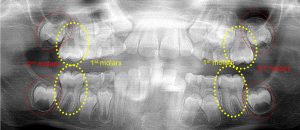

This 34 year old patient has all four third molars present (circled) and fully erupted into occlusion. They appear disease free…but are difficult to keep clean. 3rd molars are the most likely teeth to decay or have gum disease with a >98% probability that decay and gum disease will occur around all four teeth over this patient’s life time.

This 19 year old patient has all four 3rd molars present (circled). Only the upper left 3rd molar has fully erupted. The lower left 3rd molar is partially exposed and decaying while the lower right soft tissue impacted, both requiring extraction. Note the double crown on the upper right third molar.